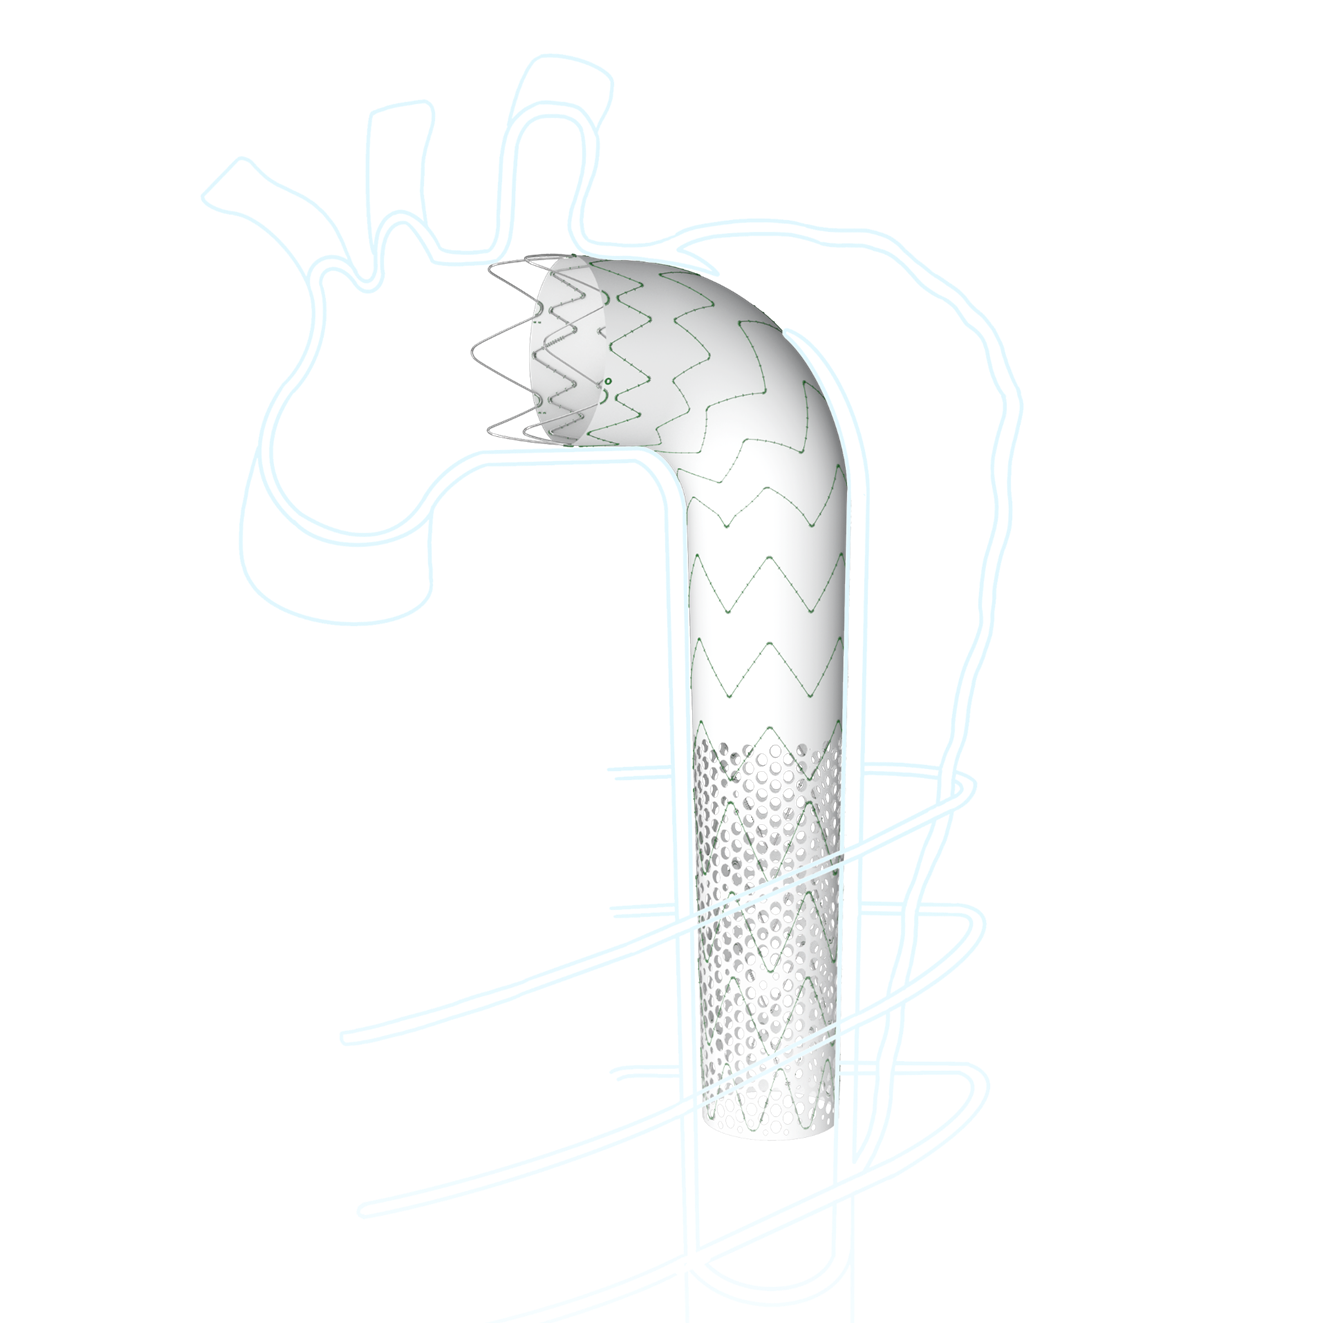

Talos™ Thoracic Stent Graft System is indicated for the treatment of Stanford type B aortic dissection, and can improve the reshaping of the distal true lumen by extending the stent length.